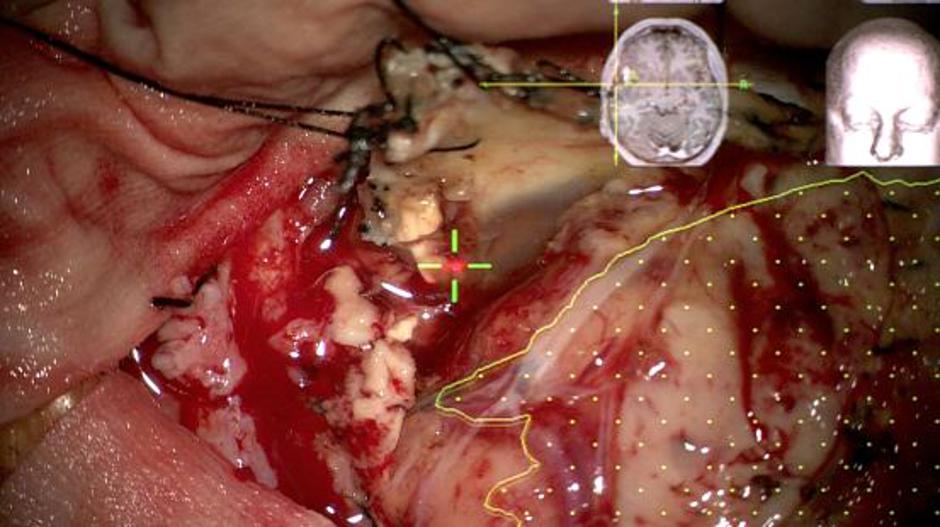

"Izvajanje robotske navigacije in 5-ALA fluorescence omogoča poseben mikroskop Zeiss Pentero 900, ki smo ga na KO za nevrokirurgijo Kirurške klinike UKC Ljubljana kupili julija letos. Mikroskop v smeri tumorja robotsko obrača nevronavigacija Medtronic Stealth Station v.7 in sproti predvaja nevrokirurgu obris tumorja na poljubni globini in usmerjenosti mikroskopa," je še povedal nevrokirurg in predstojnik oddelka Bošnjak.

"To je še posebej pomembno ob koncu operacije, v globini na meji med tumorjem in zdravimi možgani,  in v bližini predelov pomembnih funkcij možganov.  Robotska navigacija omogoča nevrokirurgu skozi okular mikroskopa med operiranjem videti obris tumorja, ki ga izračuna računalnik iz MRI slik bolnika (računalniški 3D model glave in možganov bolnika)," so še pojasnili na UKC Ljubljana.